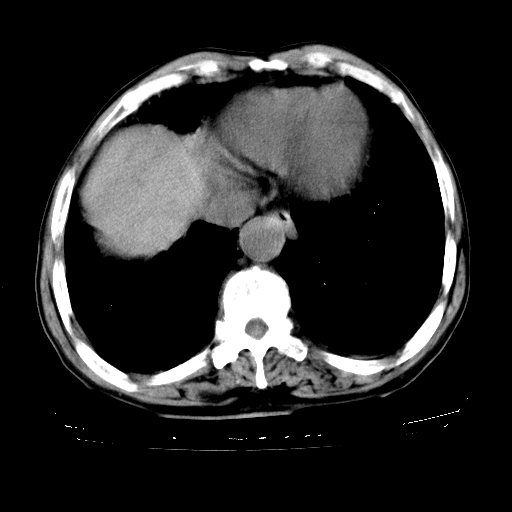

男,72岁,反复咳嗽、憋气一年余,有15年的煤矿井下工作史。

1、双肺中上叶结节影结合病史考虑巨块型矽肺结节。

2、慢支炎并肺气肿

3、双下肺纤维化灶并左下肺局限性肺气肿。

肺间质纤维化,并硬结节形成———考虑矽肺。(建议结合临床)。

支持 尘肺,肺心病?-------15年的煤矿井下工作史,双上肺叫对称的片团结节影,内见斑状钙化,边缘见粗长毛刺影,肺纹理混乱,可见网状及磨玻璃样影,肺门纵膈见多个淋巴结钙化